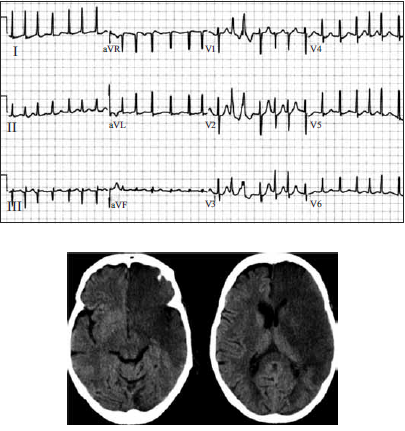

Mulher, 63 anos, foi admitida no pronto-atendimento após ser encontrada pelos familiares, caída, em casa. Ao exame físico, apresentava rebaixamento do nível de consciência (Glasgow = 11), ausculta cardíaca irregular e desvio conjugado do olhar para a esquerda. O eletrocardiograma e a tomografia computadorizada de crânio encontram-se ilustrados a seguir.

Das medidas apresentadas, assinale aquela que pode ser deletéria ao caso em questão e, portanto, deverá ser evitada inicialmente, mesmo diante de uma indicação precisa.